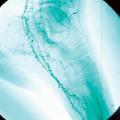

L’atteinte pulmonaire est variable : infiltrats alvéolaires, aspect en verre dépoli, nodules multiples excavés (fig. 9). L’hémorragie alvéolaire, complication majeure mais rare de la granulomatose avec polyangéite, se produit au niveau de la circulation pulmonaire distale entraînant un comblement alvéolaire (fig. 10). Elle se manifeste par une hémoptysie, une dyspnée, une anémie, des opacités diffuses alvéolaires et un liquide hémorragique au lavage bronchoalvéolaire (LBA). Des sténoses trachéo­bronchiques sont possibles.